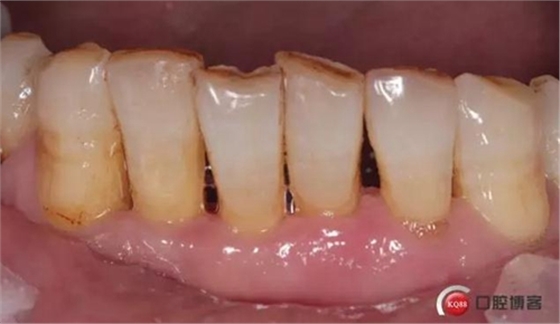

檢查:口腔衛(wèi)生狀況欠佳,牙面可見大量色素附著,牙石II°,尤以下頜前牙舌側(cè)及后牙頰側(cè)為重。牙齦紅腫,BI3-4°,PD下頜前牙區(qū)4-6mm。31松動(dòng)III°,溫度測(cè)試無(wú)反應(yīng),叩不適。32、41、42松II°+,32溫度測(cè)試遲鈍,叩(-)。

口腔宣教,全口齦上潔治,齦下超聲刮治,手工根面平整。雙氧水沖洗止血。指導(dǎo)刷牙方式。囑衛(wèi)生維護(hù),一周復(fù)診。

檢查:口腔衛(wèi)生狀況尚可,下頜前牙區(qū)牙齒鄰接可見食物殘?jiān)街Q例l色澤轉(zhuǎn)淡。

檢查:口腔衛(wèi)生狀況一般,下頜前牙區(qū)牙齦色澤尚可,牙齦位置退縮,松動(dòng)度減輕。